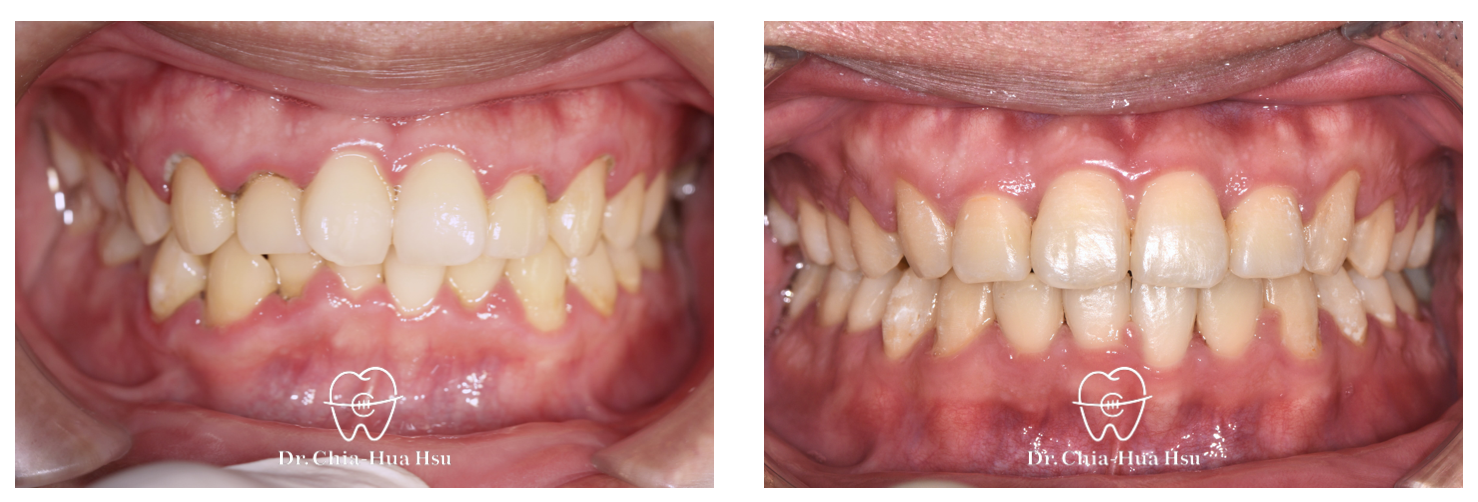

治療前

治療後